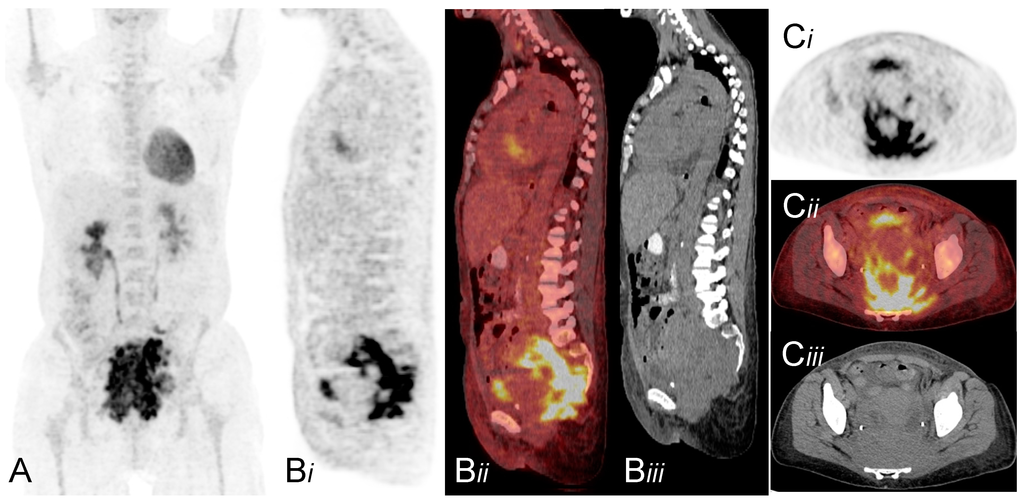

Pelvic Actinomycosis Associated with an Intrauterine Contraceptive Device Demonstrated on F-18 FDG PET/CT